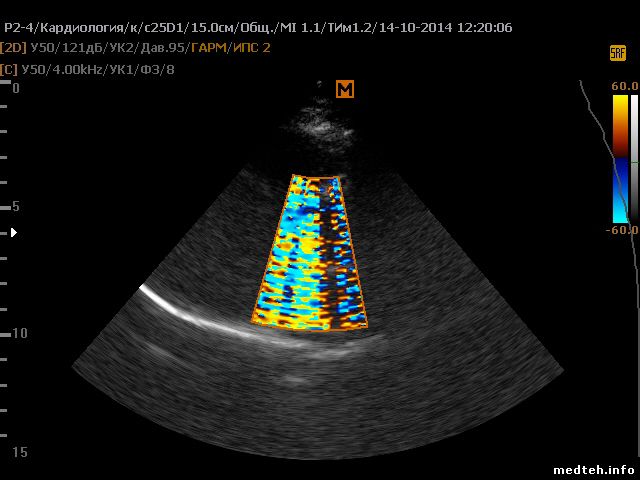

Здравствуйте! Помогите пожалуста кто чем может ) Sonoace X8 выдаёт картинку с помехами в режиме цветного доплера с настройкой TCD на кардио датчике P2-4AH. Причем на записи никаких помех нет. Покаывает вот такую картинку:

2583813.jpg(138Kb)

Здравствуйте! Что-то похожее и у меня. Сканер Sonoace R7, фазированный датчик P2-4AH. На кардиопрограмме при включении цветного допплера видим странную колористику, что на скриншотах в приложении. Также я записал клип https://yadi.sk/i/QQGNiI1UbznFv , на котором видна вертикальная "рябь" с определенной частотой. Исходные данные:

- сканер 2013 г.р., гарантия закончилась 5 месяцев назад

- подключен по схеме "сетевой фильтр" - "бесперебойник Schneider Electric", земляной провод в розетке, отдельного заземления нет

- ТО еще не проводилось

- проблема появляется хаотично (1 раз в неделю в течение 2-х недель раньше, на этой неделе второй день подряд)

- лечится тоже само и хаотично: врач посмотрит 20 - 120 минут других пациентов другими датчиками, потом проверяет фазированный - а он работает ;(

- остальные 2 подключенных датчика нормально работают во всех режимах, в том числе и в допплеровских

- переключение датчика в другое гнездо не помогает

- вчера проблему решило полное выключение и включение аппарата вместе с бесперебойником, сегодня уже не помогло

Прошу помощи и совета.

Очень похоже на программный сбой, особенно 2 картинка. При таких скоростях и частоте доплера на этом усилении изображение должно быть чистым. Попробуйте сменить режим цветного доплера на энергетический. Если при этом изображение нормализуется, то ПО. Если нет - вероятно датчик. Но я бы первым делом обновил ПО.